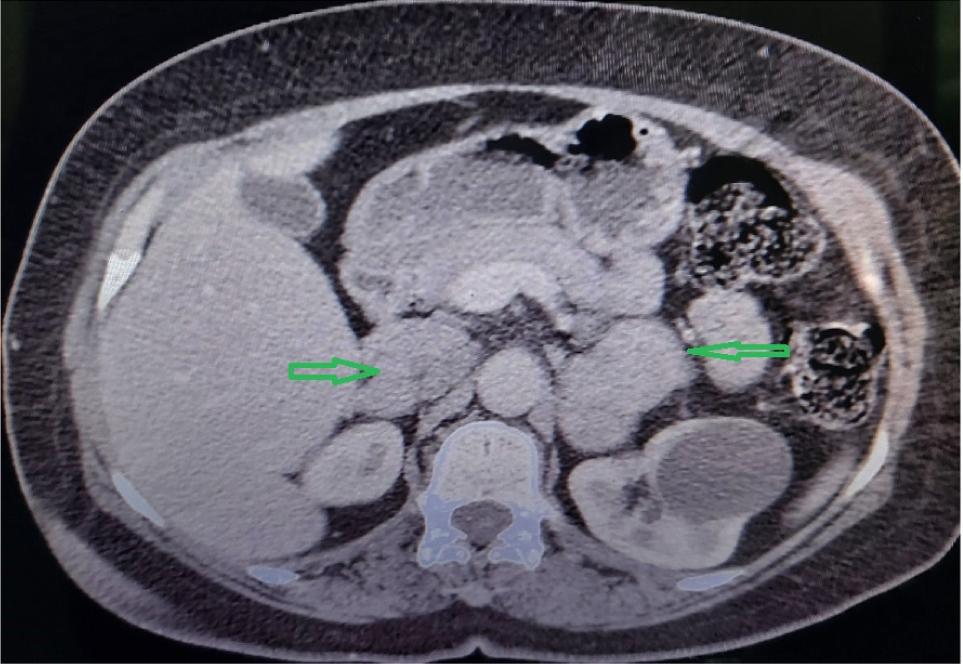

Contrast-enhanced abdominal computed tomography (CT) scan showed two soft tissue heterogeneous enhancement masses measuring 30 × 22 mm and 18 × 15 mm in the right adrenal gland and two soft tissue heterogeneous enhancement masses measuring 40 × 33 mm and 35 × 28 mm in the left adrenal gland (Figure 1).

Figure 1: Abdominal computed tomography image showing the bilateral adrenal masses (arrows).